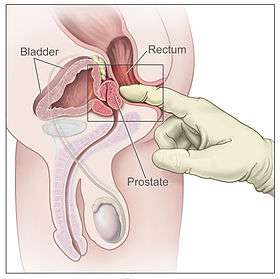

A healthy human male prostate is classically said to be slightly larger than a walnut. The mean weight of the normal prostate in adult males is about 11 grams, usually ranging between 7 and 16 grams.[6] A study stated that prostate volume among patients with negative biopsy is related significantly with weight and height (Body Mass Index), so it is necessary to control for weight.[7] The prostate surrounds the urethra just below the urinary bladder and can be felt during a rectal exam.

Prostate cancer is one of the most common cancers affecting older men in developed countries and a significant cause of death for elderly men[31] (estimated by some specialists at 3%). Despite this, the American Cancer Society's position regarding early detection is "Research has not yet proven that the potential benefits of testing outweigh the harms of testing and treatment". They believe "that men should not be tested without learning about... the risks and possible benefits of testing and treatment" which should be discussed with a doctor at age 50 or at age 45 if the patient is black or has a father or brother who acquired prostate cancer before age 65.[32] If checks are performed, they can be in the form of a physical rectal exam, measurement of prostate specific antigen (PSA) level in the blood, or checking for the presence of the protein Engrailed-2 (EN2) in the urine.